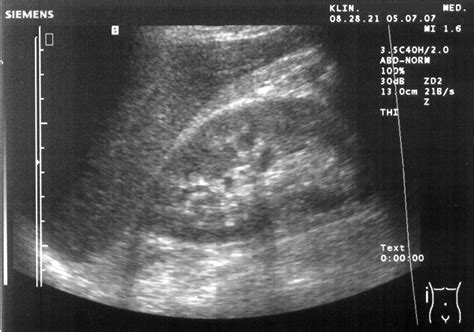

Ultrasound of the abdomen showing the Pouch of Morison

Ultrasound: Ultrasound is a non-invasive and readily available imaging technique that can detect fluid in the Pouch of Morison. The presence of fluid in this area can be visualized as an anechoic (black) space between the liver and the right kidney.